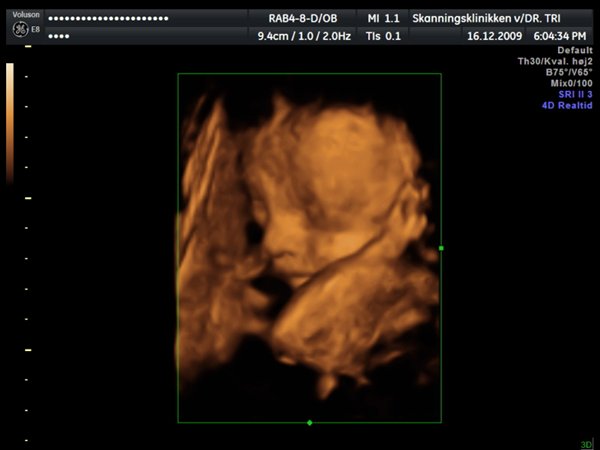

Ja, så var vi til 3D scanning med Ida igår. Og hvad kan jeg sige andet end hun er en meget træt pige

Jeg tror vi talte hun gabte mellem 10 og 11 gange under hele scanningen. Derudover havde hun meget travl med at gemme sig bag sine hænder som hun hele tiden åbnede og lukkede så det så ud som om hun vinkede

Billederne blev ikke så gode som jeg havde håbet, for lige som sin bror ligger hun meget tæt på moderkagen og med navlestregnen forand hovedet. Men de er ok, vi kan da se at hun ser sund og rask ud og at hun trives derinde.

Vedhæftede fotos (klik for at se i fuld størrelse)